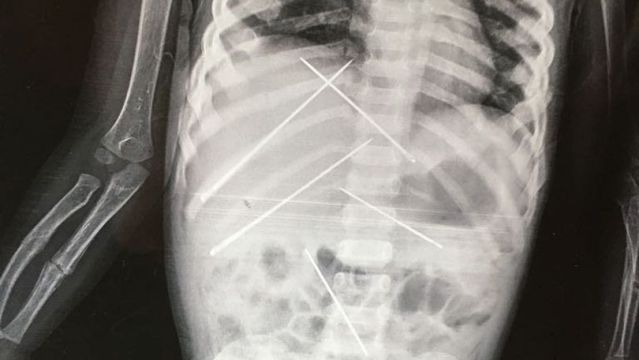

Las radiografías mostraban agujas dentro de su cuerpo que no pudieron ser extraídas por miedo a ocasionar un daño aún mayor. Al parecer, el responsable de los abusos sexuales y de las prácticas de vudú era el jefe de su madre, que la empleaba como trabajadora doméstica.

Agujas dentro del cuerpo de la niñaNewslions/Swns.com

Una niña de tan sólo tres años ha fallecido a causa de las prácticas de vudú y magia negra que practicaba con ella el jefe de su propia madre, quien, al parecer, le introdujo al menos unas siete agujas dentro de su cuerpo, según informa el diario 'India Today'.